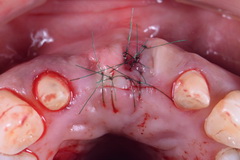

29前歯を歯肉移植(結合組織移植)とジルコニアブリッジで治した症例

※診療結果には個人差があります。

患者:55歳女性

主訴:

前歯を綺麗にしたい。

費用:ジルコニアブリッジ約50万円 歯肉移植(結合組織移植)9万円(税別)

メリット:天然歯と見分けがつかない程美しい。汚れがつきにくいためお掃除が楽。

デメリット:手術が必要である。

備考:歯肉移植は必須ではありませが、より審美的、発音がしやすい形態を作るためにオペを行っております。この症例の技工士は小出俊介氏です。

治療前

治療内容

治療後

オペより2か月。美しい歯肉が再生しています。